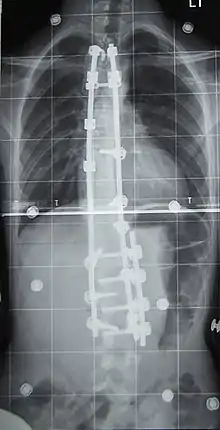

Surgery is usually recommended by orthopedists for curves with a high likelihood of progression (i.e., greater than 45–50° of magnitude), curves that would be cosmetically unacceptable as an adult, curves in people with spina bifida and cerebral palsy that interfere with sitting and care, and curves that affect physiological functions such as breathing.[103][104]

Surgery is indicated by the Society on Scoliosis Orthopaedic and Rehabilitation Treatment (SOSORT) at 45–50°[4] and by the Scoliosis Research Society (SRS) at a Cobb angle of 45°.[105] SOSORT uses the 45–50° threshold as a result of the well-documented, plus or minus 5° measurement error that can occur while measuring Cobb angles.[105]

Surgeons who are specialized in spine surgery perform surgery for scoliosis. To completely straighten a scoliotic spine is usually impossible, but for the most part, significant corrections are achieved.[106]

The two main types of surgery are:

- Anterior fusion: This surgical approach is through an incision at the side of the chest wall.

- Posterior fusion: This surgical approach is through an incision on the back and involves the use of metal instrumentation to correct the curve.

One or both of these surgical procedures may be needed. The surgery may be done in one or two stages and, on average, takes four to eight hours.